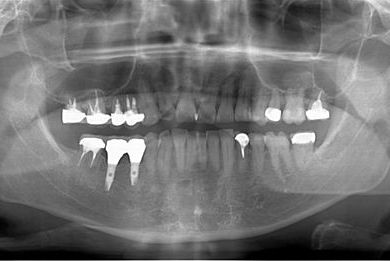

インプラント治療+セラミック治療+歯肉歯槽骨整形術

| 性別/年齢 | 男性 / 47歳 | ||||||||||||||||||||||||||||||||

| 主訴 | 悪いところの治療と、歯をきれいにしたい。 | ||||||||||||||||||||||||||||||||

| 治療方針 | 右下奥、保存不能な歯を抜歯し、インプラント治療にて、機能的・審美的回復を行う。 | ||||||||||||||||||||||||||||||||

| 治療内容 | インプラント2本、メタルボンドセラミッククラウン9本(メタルボンド用土台6本)、ハイブリッドセラミッククラウン2本(セラミック用土台2本)、ハイブリッドセラミックインレー5本、歯肉歯槽骨整形術 | ||||||||||||||||||||||||||||||||

| 治療期間 | 2年9ヶ月 |